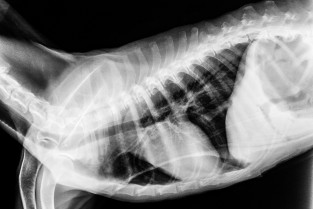

Les Ateliers du Sud-Est abordent cette année le thème transversal du thorax chez le Chien et le Chat.

- Interpréter des radiographies thoraciques.

- Prendre en charge un traumatisme thoracique (notamment pneumothorax et hernie diaphragmatique).